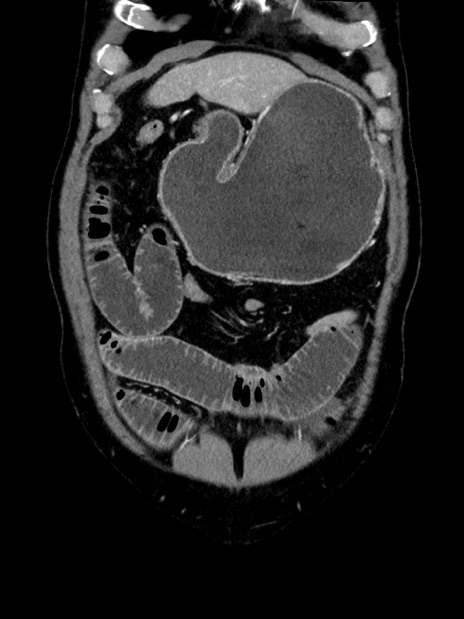

症例35(冠状断像)

【症例】70歳代 男性

【主訴】腹部膨満、嘔吐

【現病歴】昨日より腹部膨満感出現。本日増悪し、仙痛出現。嘔吐あり、受診。

【既往歴】糖尿病、胆摘後

【身体所見】BP 149/80mmHg、HR 74/min、BT 35.9℃、腹部:膨満、軟、圧痛なし。腸雑音減弱あり。上腹部正中切開瘢痕あり。

【データ】WBC 13500、CRP 1.72